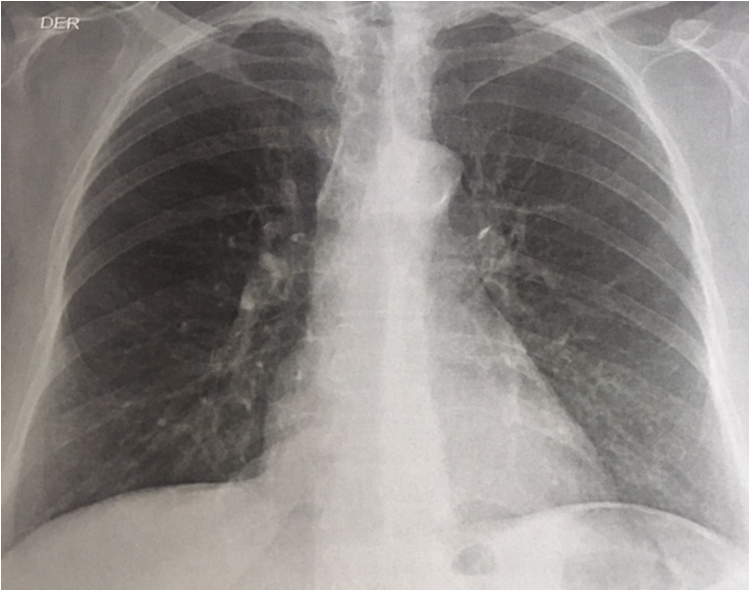

Se solicitó la realización de una baciloscopia seriada de esputo, que fue negativa, y posterior cultivo. La radiografía de tórax evidenció la presencia de nódulos pulmonares e infiltrados intersticiales micronodulares, compatibles con silicoantracosis (figura 1). También se le realizó perfil hepático y hemograma, que estaban dentro de la normalidad. En el momento de la consulta, se realizó manejo con broncodilatadores.

En la literatura sobre el tema hay algunos estudios de salud ocupacional sobre silicoantracosis realizados en minas de Colombia como en Cerrejón, La Guajira, con el fin de minimizar el riesgo y las consecuencias de la exposición a agentes tóxicos (4). Según la Organización Mundial de la Salud, su prevalencia está alrededor del 42 % en personas expuestas, lo que representa un promedio de 1.240.000 años de vida saludables perdidos y costos significativos para el sistema de salud de cada país, teniendo una tasa de mortalidad en Estados Unidos de 13,2 por millón en 2000 (1). El diagnóstico parte de la observación de hallazgos radiológicos sugestivos, como lesiones nodulares o infiltrados pulmonares intersticiales; pero su diagnóstico definitivo es mediante biopsia pulmonar, como se evidenció en este caso. El tratamiento consiste en manejo con inhaloterapia y oxigenoterapia. Como principal complicación se presenta el cor pulmonale, la falla ventilatoria severa y la muerte (5).

En cuanto a la infección por Mycobacterium nonchromogenicum, en las imágenes diagnósticas se evidencia un nódulo que suele ser único, generalmente ubicado en los lóbulos superiores, y al realizar un cultivo en esputo, se evidencia el microrganismo (6).